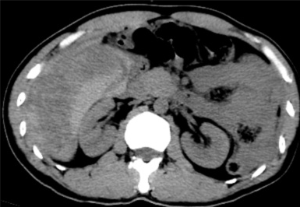

手術順利,術后患者轉正重癥醫學科給予輸血、補液、止痛及康復治療。術后3天,患者復查血,肝功能正常。后續恢復良好,并在短期內出院。